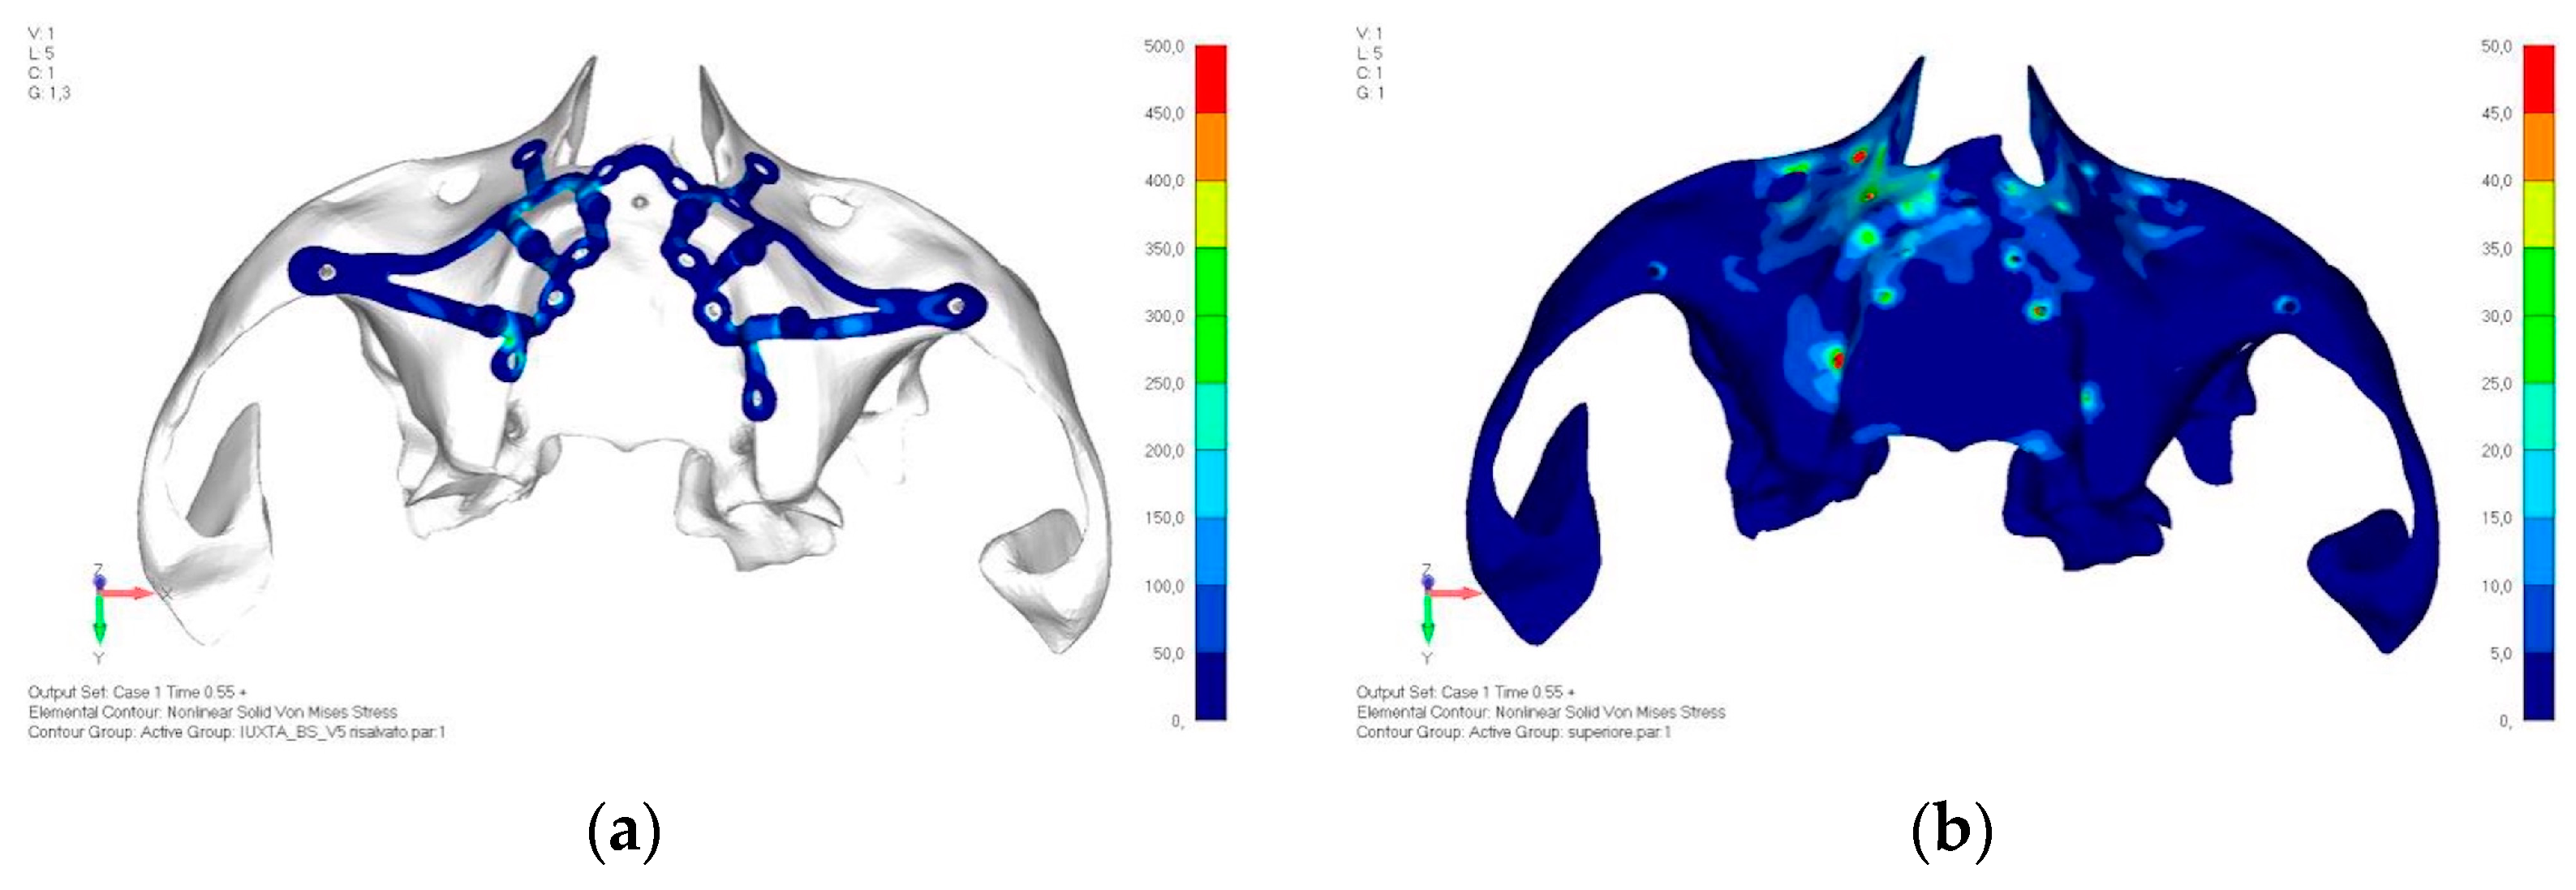

- Model V2. This model serves as an alternative to model V1, as it aims to stabilize the structure posteriorly using screws placed in the vestibular direction rather than the palatal direction (Figure 10). The model displayed similar behavior to V1, leading to the decision to proceed with V1 for further development (Figure 11a,b).